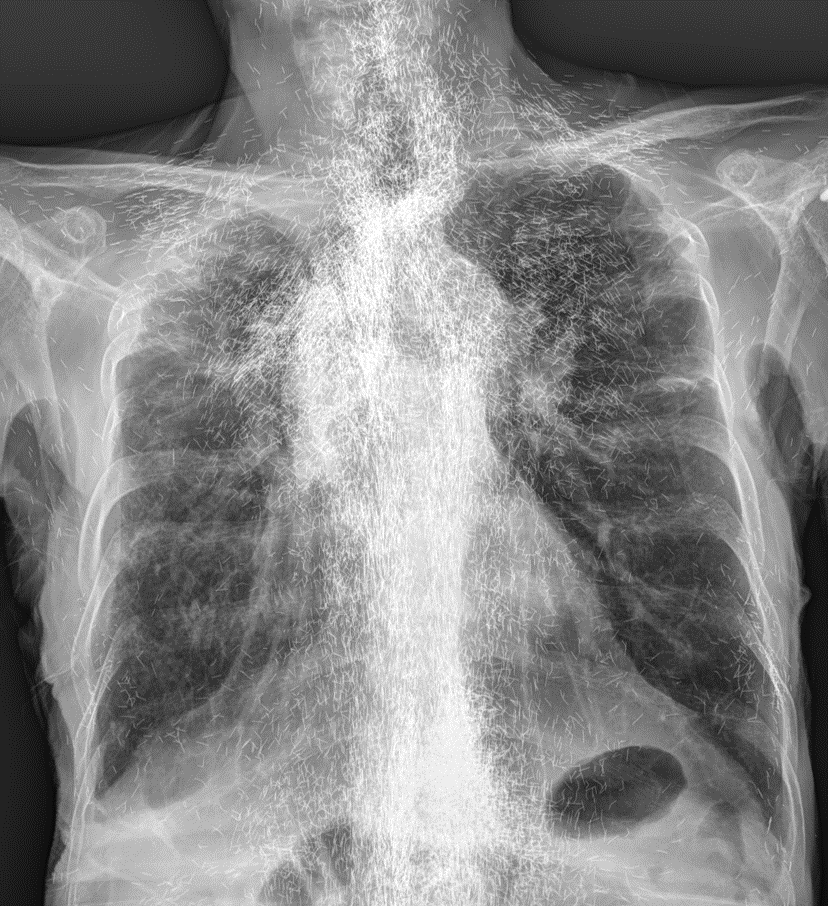

가슴2.png

금빛 인간이다.

세상은 넓고, 충격적인 일은 많다. 근데 저거 진짜 금일까?